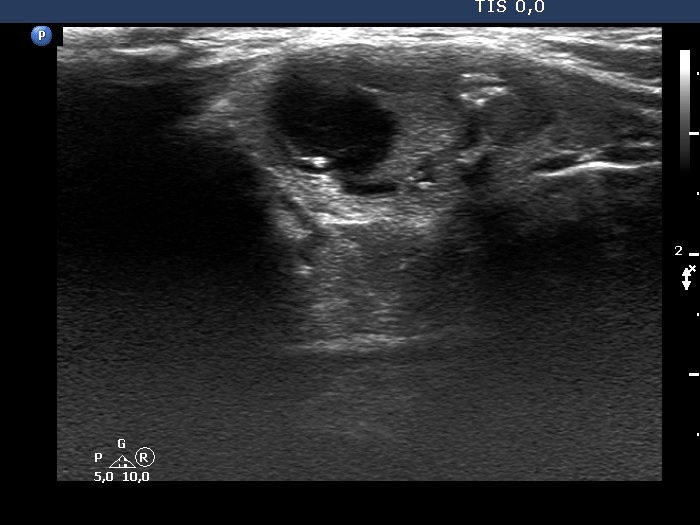

Four years after the first examination (third row of images):

Clinical presentation. The patient had no complaints.

Palpation: unchanged.

Hormonal evaluation: TSH 0.72 mIU/L.

Ultrasonography. The lesion increased by 35% larger in volume compared with the first examination, primarily because of the increase of the cystic content.

Suggestion: TSH in a year, ultrasound in 3 years.

Comment.

1. The nodule in the lower part of the right lobe is an EU-TIRADS 4 lesion.

2. The classification of the nodule in the isthmus depends on the interpretation of doubtful echogenic granules, if we regard them microcalcifications, then the nodule is an EU-TIRADS 5, if we do not, then an EU-TIRAD 4 lesion.